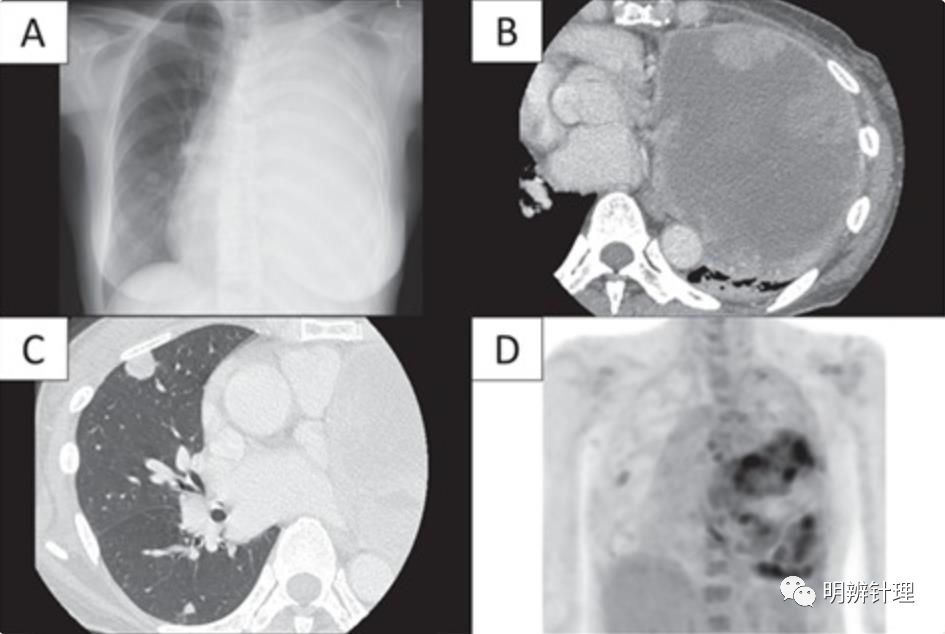

女性,64 岁。咳嗽和呼吸困难就诊

(A)胸片和 ( B ) 胸部 CT 显示左肺有一个 15 × 14 × 10 cm 的巨大肿块,肿瘤中心有广泛的低密度区域,怀疑出血和坏死; 胸片显示左肺完全肺不张。

(C)右肺发现多个直径在 0.5 到 1.3 厘米之间的小结节。一个结节位于上叶,其他结节位于下叶。

(D)PET-CT 证实大肿块内有微弱的FDG沉积,包括右上肺结节内,SUV最大值分别为 6.5 和 2.3。

诊断结果:肺硬化性肺细胞瘤